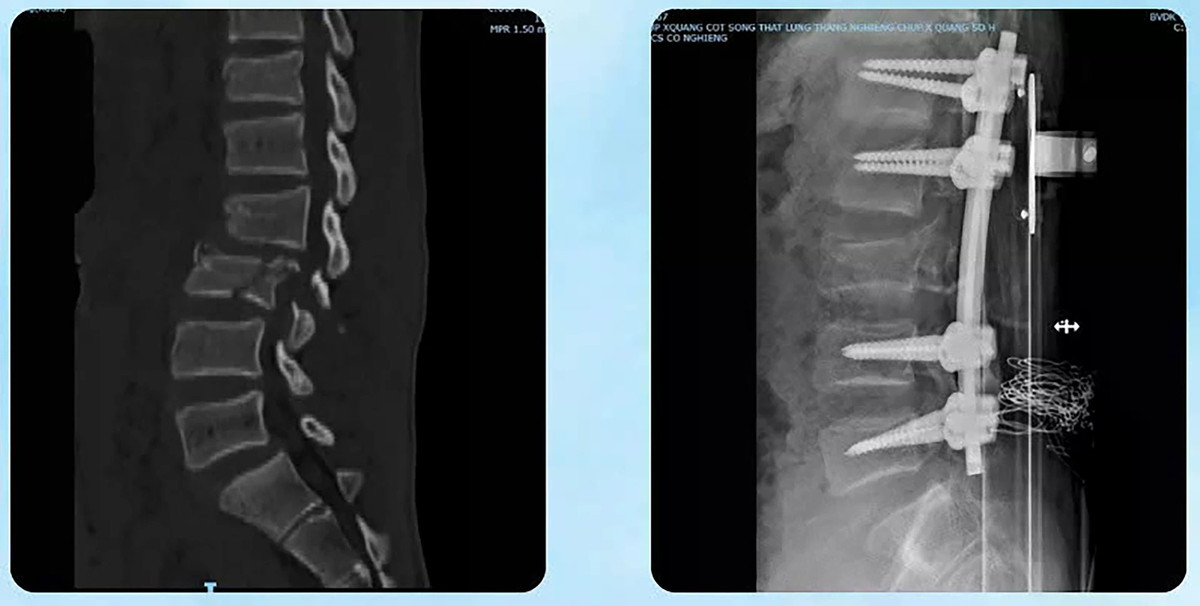

Kết quả chẩn đoán cho thấy bệnh nhân bị tổn thương nặng ở nhiều cơ quan: Chấn thương ổ bụng, gãy thân xương đùi, tổn thương phần mềm vùng bụng lưng chậu, chấn thương lồng ngực và thận. Đặc biệt, bệnh nhân bị gãy trật cột sống nặng tại đoạn L2–L3, kèm máu tụ ngoài màng tủy, tủy dập và rách màng tủy - tình trạng có nguy cơ để lại di chứng rất nặng.

Hình ảnh gãy trật cột sống nặng đã được nắn chỉnh - Ảnh BVCC

Khoa Ngoại Thần kinh: Tiến hành phẫu thuật vào cột sống lối sau, nắn trật cột sống đoạn L2–L3 và làm vững toàn bộ đoạn cột sống bị tổn thương bằng nẹp vít cuống cung dưới hướng dẫn C-arm; Đồng thời cắt bản sống L2–L3, lấy máu tụ ngoài màng tủy giải phóng chèn ép tủy, xử lý vùng tủy dập và vá màng tủy bị tổn thương.